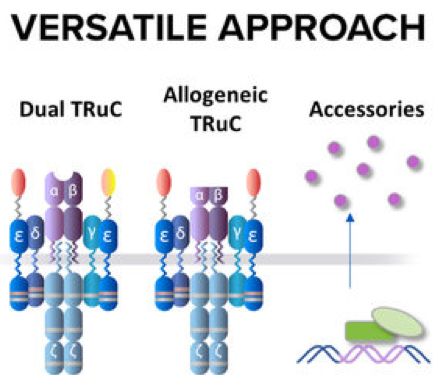

Its proprietary TRuC (TCR Fusion Construct) utilizes the power of T cell signaling pathways and receptors to eliminate cancer cells. This clinical stage immunotherapy company intends to use its T cell therapies to treat hematologic cancers and solid tumors.

Image Source: https://www.tcr2.com/our-approach

Image Source: https://www.tcr2.com/our-approach

Its technology is driven by the TCR complex and phosphorylation motifs (ITAMs) that can bind to tumor antigens and catalyze a complex signaling cascade that can annihilate cancer cells. It’s TRuC™ Platform is an optimal amalgamation of the CAR-T and TCR-T cell therapies minus their shortcomings. It overcomes the limitations of the existing treatment options such as inability to target solid tumors, severe cytokine release syndrome, increased neurotoxicity, HLA down regulation and lack of HLA matching.

The company’s clinical data has shown its superior anti-tumor ability over CAR-T cells with minimal levels of cytokines. It has also demonstrated faster migration to the tumor, improved metabolic fitness and enhanced tumor penetration as compared to CAR – T. Its non-dependence on HLA matching allows it to be used for a larger patient population as well as introduction of improvements to include targeting multiple tumor antigens simultaneously, reduction in treatment expenditure by using off-the-shelf allogenic cells, and accessories to overcome the suppressive effect of the tumor microenvironment.